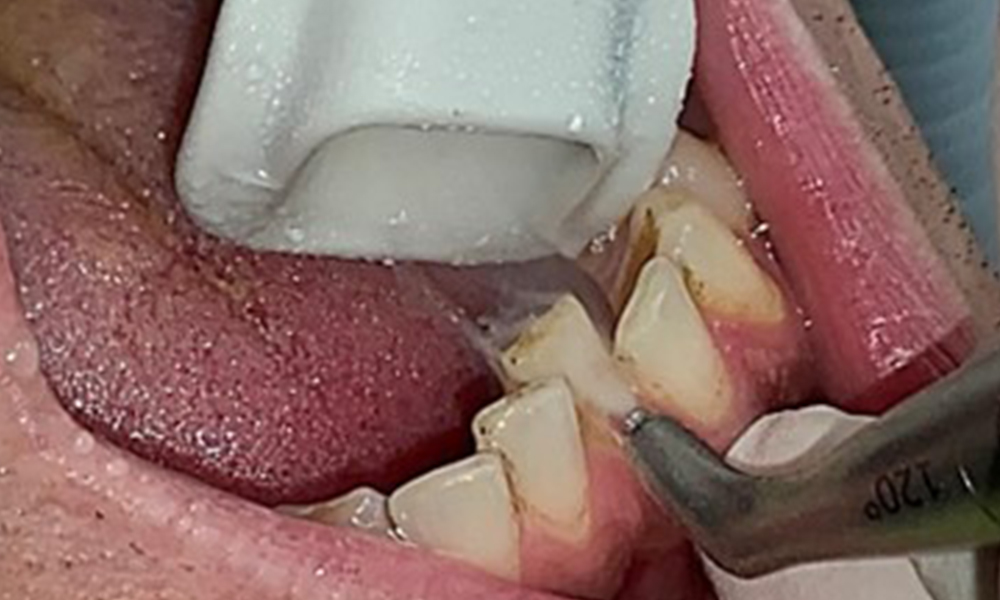

Due to the otherwise favourable general medical condition, the needs determined during the intraoral examination will be decisive for their treatment. It will be essential to periodically determine the probing depths. Gingival bleeding decreases in smokers, which is why the clinical diagnosis of periodontitis can only be made by probing (Fig. 7). Placing exclusive focus on the determination of bleeding indices may obscure existing periodontitis or gingivitis. (5)

Instruction and motivation are important components of these appointments. Good home-based intraoral hygiene behaviour and understanding are important for patients. Plaque accumulation is particularly evident in the cervical regions (Fig. 8).

The objective would be to control disease risk by removing supragingival and subgingival biofilm. The instruments can be selected based on patient needs. First, calculus and any concretions must be removed using ultrasonic and/or manual instruments (Fig. 10).